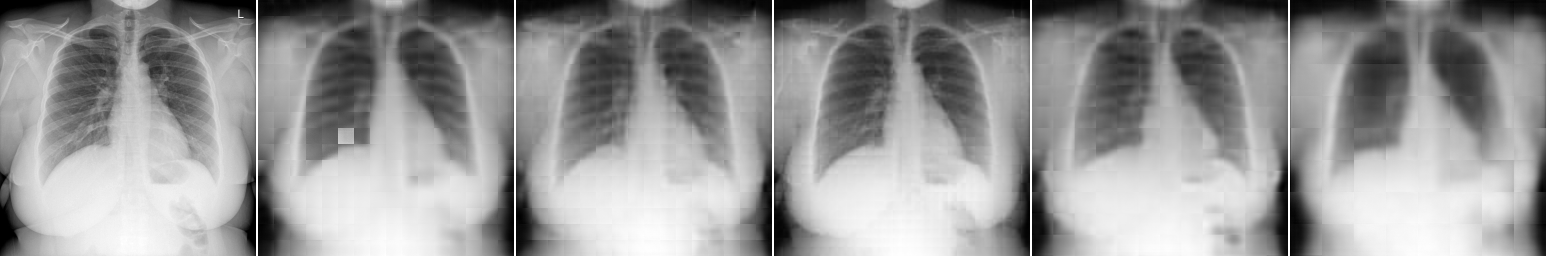

Image Patch Regeneration: Here, we vary the block size for image encoding and decoding to see how it will affect the image regeneration task. As shown in Fig. 5 and Table 4(b), block size renders the best image regeneration quality compared to other variants. Block size demonstrates higher classification accuracy with a moderate requirement of the computing resources (larger # patches per image will require larger GPU memories). As shown in Fig. 5, our proposed multi-scale image encoder and decoder can provide better regeneration results than a single-scale model. It generally suffers less from the blocking artifacts and is able to preserve more details, especially for pathological regions, as shown on the top two examples in Fig. 5.

The positional encoding used by existing works for image patch locations may not be sufficient to preserve the spatial information of images. This is because nearby image patches are often closely related, but direct patch predictions solely based on the features of each cell are not effective enough, which often lead to blocking artifacts (as shown in the result section later). It is one of the natural disadvantages of transformer-based methods for image processing compared to CNN-based ones. Here, we attempt to suppress this shortcoming within the general framework of transformer architectures. In Fig. 4, we illustrate a multi-scale image encoding and decoding process.

In such a way, we can propagate the spatial information contained in upper scale patches into lower scale ones since each patch from the upper scale is closely related to at least four patches in the lower scale under the current setting.